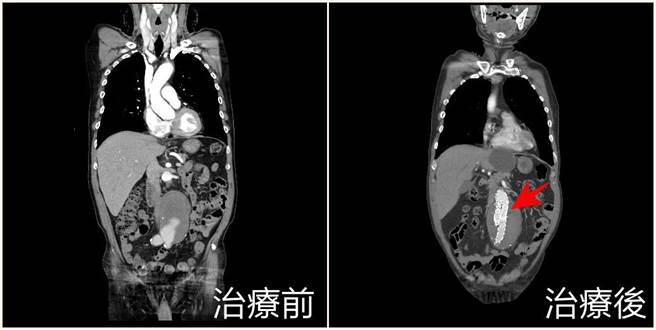

菸龄50多年黄姓老翁长出直径8公分的腹主动脉瘤以及明显主动脉弓剥离,经微创主动脉覆膜支架手术后成功恢復,术伤口仅约3至5公分甚至更小,对长者是一大福音。(亚大附医提供/潘虹恩台中传真)

黄俊晟说,考量患者年事已高採用「微创主动脉覆膜支架手术」,先在双大腿腹股沟做两个小切口,再将导丝延伸到主动脉弓剥离处以及腹主动脉瘤体位置,分别置放2支及3支覆膜支架,前者让主动脉的血液不会再继续灌入内膜假腔裂孔,后者则是阻绝血液继续供应瘤体养分;患者术后3天即康復出院,目前稳定恢復中,术伤口仅约3至5公分甚至更小,对长者是一大福音。